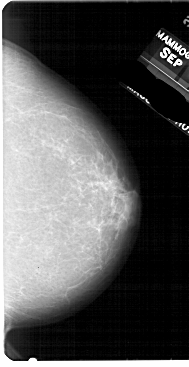

A_1948_1.LEFT_MLO

LEFT_MLO LINES 5491 PIXELS_PER_LINE 2896 BITS_PER_PIXEL 12 RESOLUTION 43.5 OVERLAY